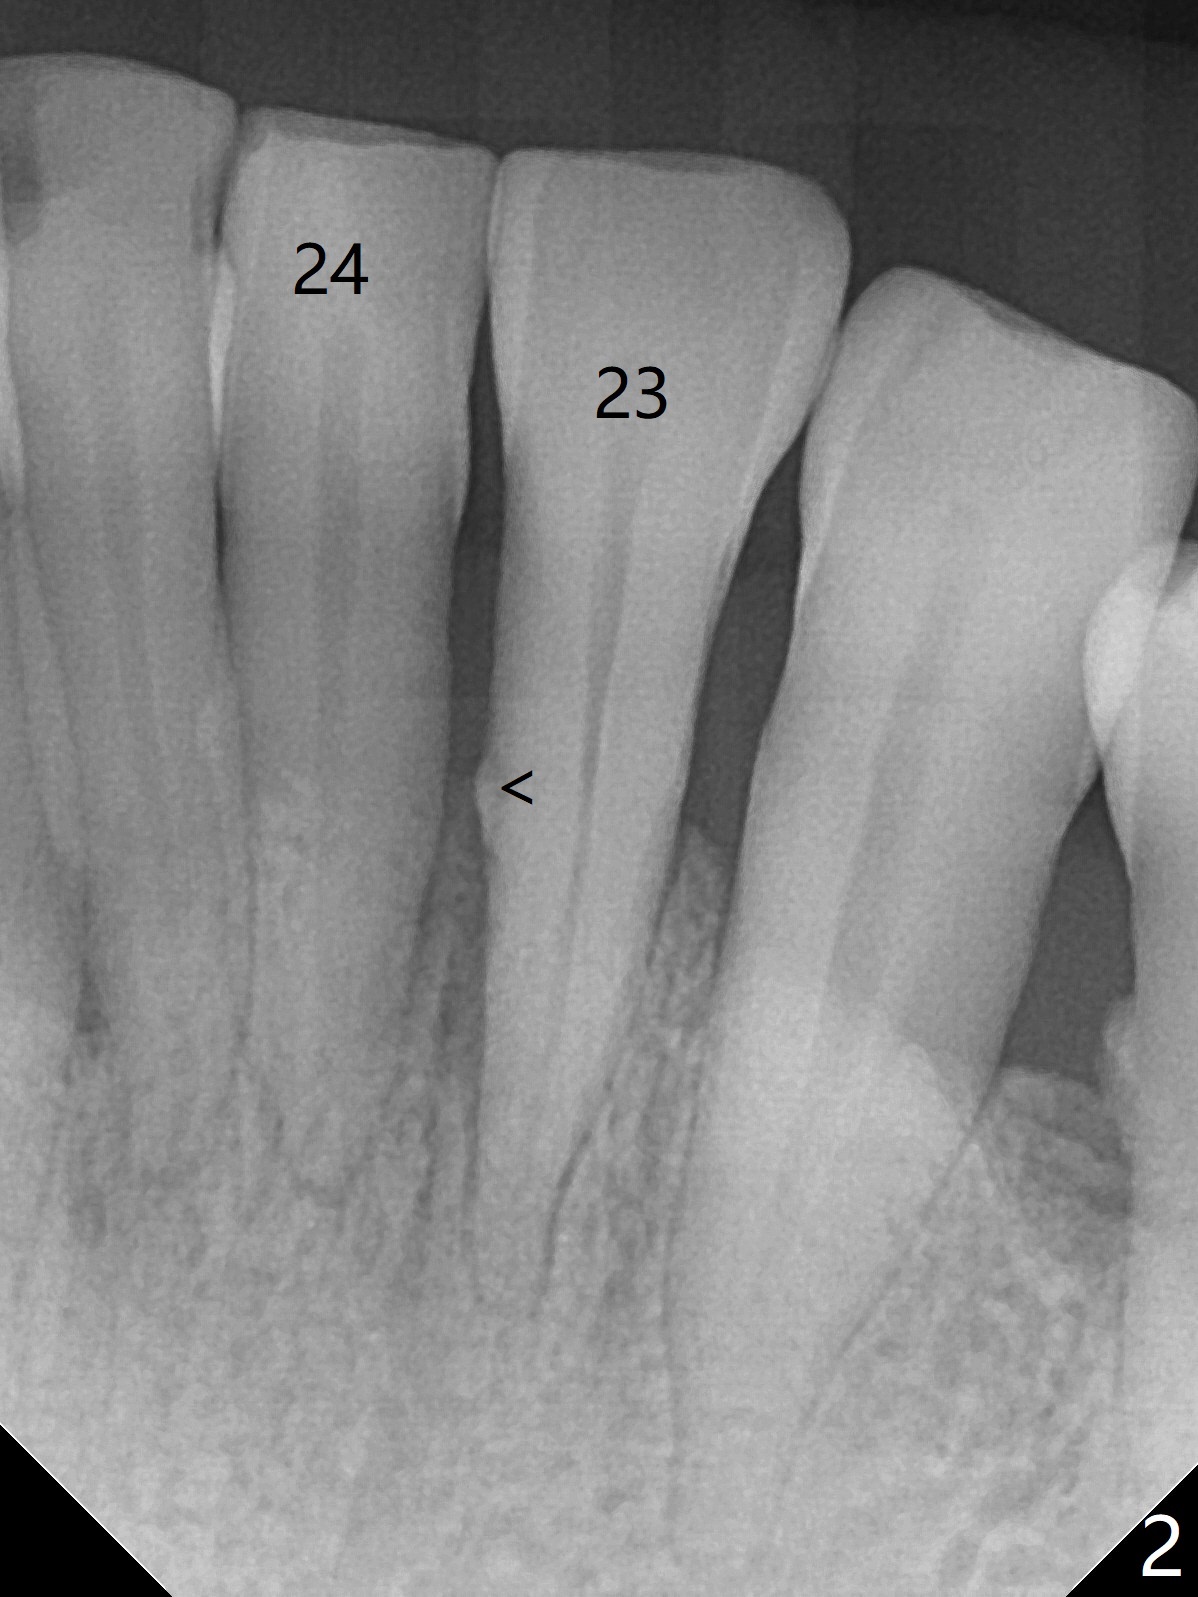

A 45-year-old woman returns for perio maintenance with erythematous and edematous papilla between #23 and 24. Two days later the infection subsides with sinus track (Fig.1 <). With infiltration anesthesia, Waterlase is used for outer and inner (steps 1,3) pocket de-epithelization (and retratction), and sulcular debridement/degranulation (step 5, Fig.3). Gingivectomy (step 2) is omitted because of severe existing gingival recession. Scaling and root planing is not conducted since step 3 seems to be able to remove fine subgingival calculus (Fig.2 <). But it appears not sufficient (Fig.4). Bone decortication should be implemented in future cases (step 6). Mepivacaine is administered in block fashion immediately postop for pain control. The patient is doing fine postop.